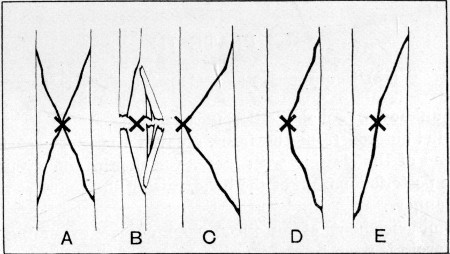

50. Types of Gunshot Fracture161

47 Charles Street, Berkeley Square, W.